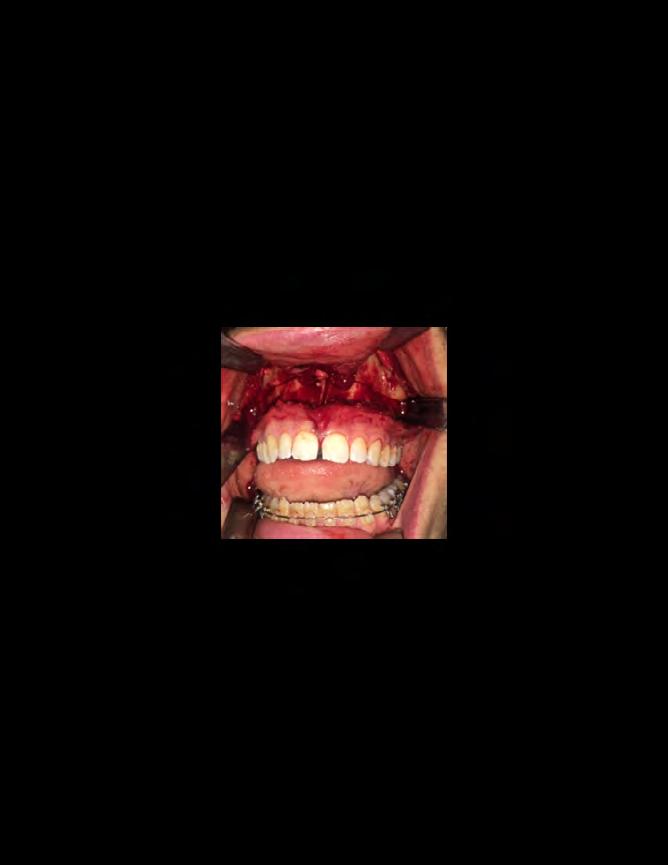

Approximately six months after insertion of the RPE, digital scans were taken for SureSmile custom wires and the patient was scheduled for the SFOT procedure with the oral surgeon. The RPE was removed, SureSmile wires inserted and segmental corticotomies performed, immediately followed by further vertical elastics on the right side (Figure

4). Archwires were upgraded incrementally into 19 x 25 SS. Once the bite was completely closed, the patient was referred to the myofunctional therapist to begin treatment. Eight sessions of myofunctional exercises were performed, focusing on muscle building, toning, synchronicity and awareness. Improvement in correct chewing, swallowing and resting postures of the lip and tongue were addressed. All appliances were removed 21 months after initial insertion (Figure 5), and the patient was referred to a re-

Figure 4. Post-corticotomy, with SureSmile custom wires.